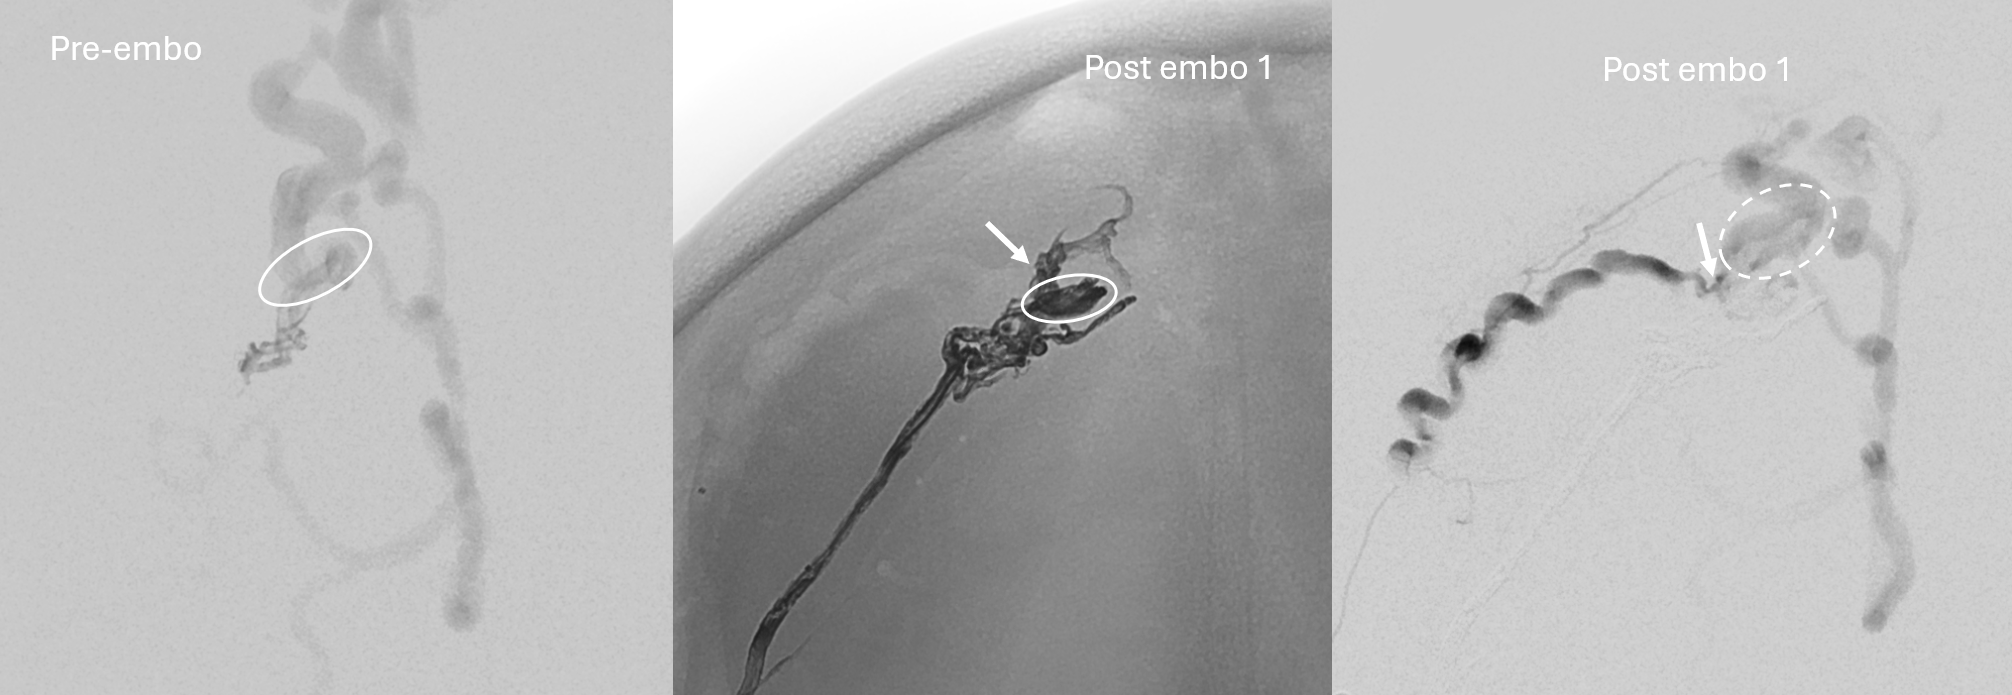

Micro angio and onyx 18 cast. A mistake is made here

This shows the mistake. Can u see?

nBCA — its not that Onyx or nBCA is better. From this position Onyx will not reach for sure so nBCA is the way to go

Glue reflux

Closed

Now, look at the images below and tell me what the mistake during first injection was. The images on right should read post embo 1